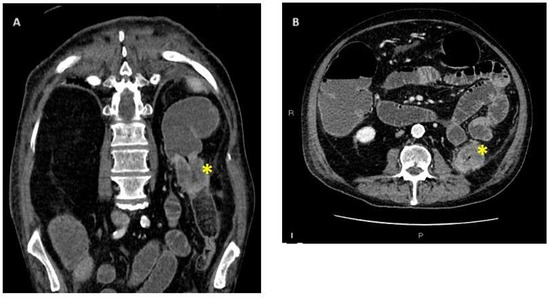

3.2. Differential Diagnosis and Characteristics of Malignant Acute Colonic Obstruction from CT Scan